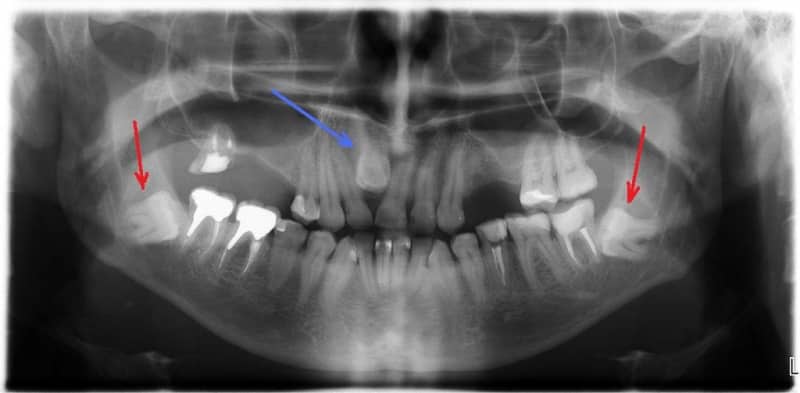

Зуб-восьмёрка, из-за своей особенной структуры, может вызывать проблемы при прорезывании. Неправильное направление роста может повредить десну или щеку. Ещё одна проблема связана с труднодоступным расположением зуба мудрости, что способствует накоплению бактерий и налёта. Регулярная и тщательная гигиена полости рта необходима для предотвращения кариеса. Однако, даже при этом, зуб мудрости может стать источником заболеваний и воспалений. В таких случаях, его рекомендуется удалить, так как лечение этого зуба может быть сложным и не всегда эффективным. Неправильное направление роста также является показанием для удаления зуба мудрости, так как оно вызывает боли и воспаления слизистой. Однако, потеря третьего моляра не является причиной для огорчения, так как он обычно не участвует в пережёвывании пищи, а только создаёт препятствие на её пути в пищевод, собирая на себе кусочки пищи, которые могут вызвать кариес и другие заболевания. Также не является проблемой, если зубы мудрости вообще не прорезываются, так как для них может не быть достаточно места из-за небольшого размера челюсти.

Удаление зуба-восьмёрки является сложной процедурой, требующей участия хирурга-стоматолога. Современные стоматологические кабинеты оборудованы всем необходимым для этой операции. В зависимости от количества корней и их сплетения может потребоваться надрезание, раздробление или распиливание челюсти, а также наложение швов.